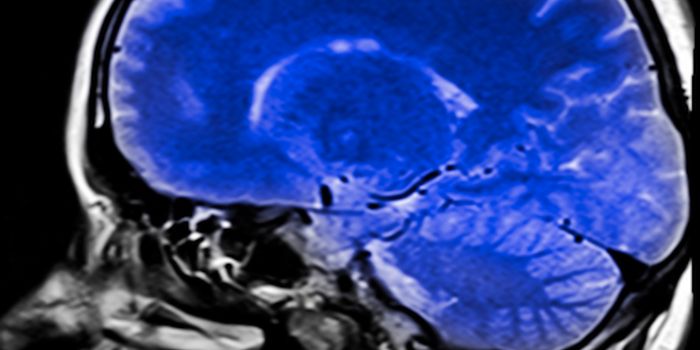

OCT 11, 2023Clinical & Molecular DXTumors in the central nervous system are particularly deadly. During surgery to remove a brain tumor, surgeons usually h ...